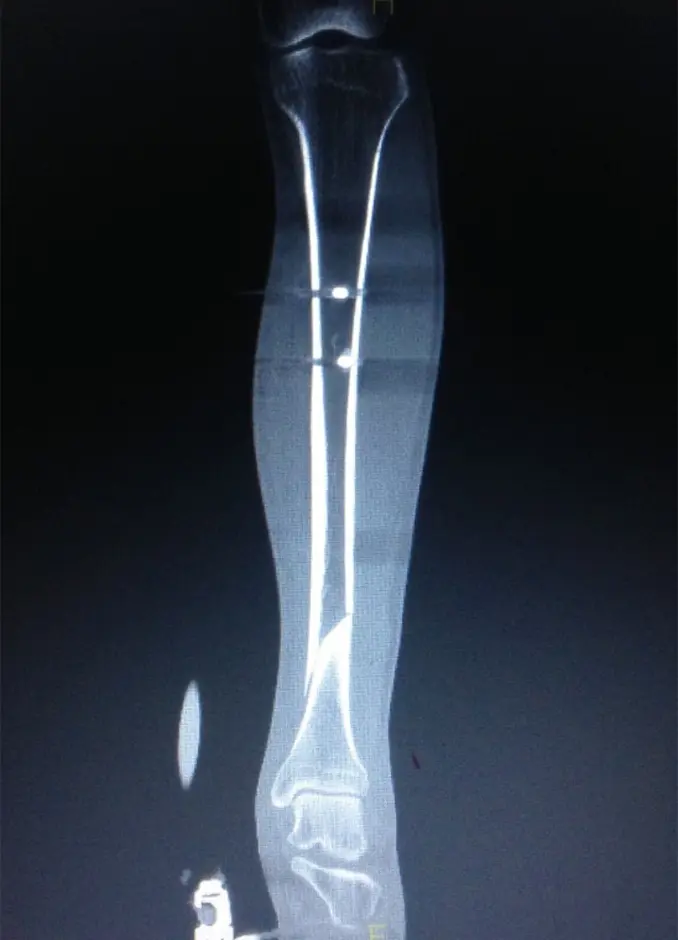

(図4)術後単純X線

患肢の腫脹が改善し、血糖コントロールがついたところで、受傷17日目に観血的整復固定術(手術時間:90分)を施行した。

ターニケット未使用、体位は仰臥位で膝関節軽度屈曲位にて手術を行った。皮切は外側関節裂隙から膝蓋骨関節縁とした。外側膝蓋支帯を切開、膝蓋腱および関節包の間を剥離、ガイドピン刺入部を露出した。ガイドピンを刺入し、ドリリングした後、ガイドワイヤーを挿入。遠位骨片にブロッキングピン刺入後、徒手的に整復しながら径12.5mmまでリーミングし、径11mm、長315mmのSynthes社製 Expert Tibial nailを挿入した。近位はスクリュー2本、遠位スクリュー4本挿入固定とした。固定性良好であることを確認し、エンドキャップを挿入、洗浄閉創し手術終了とした。